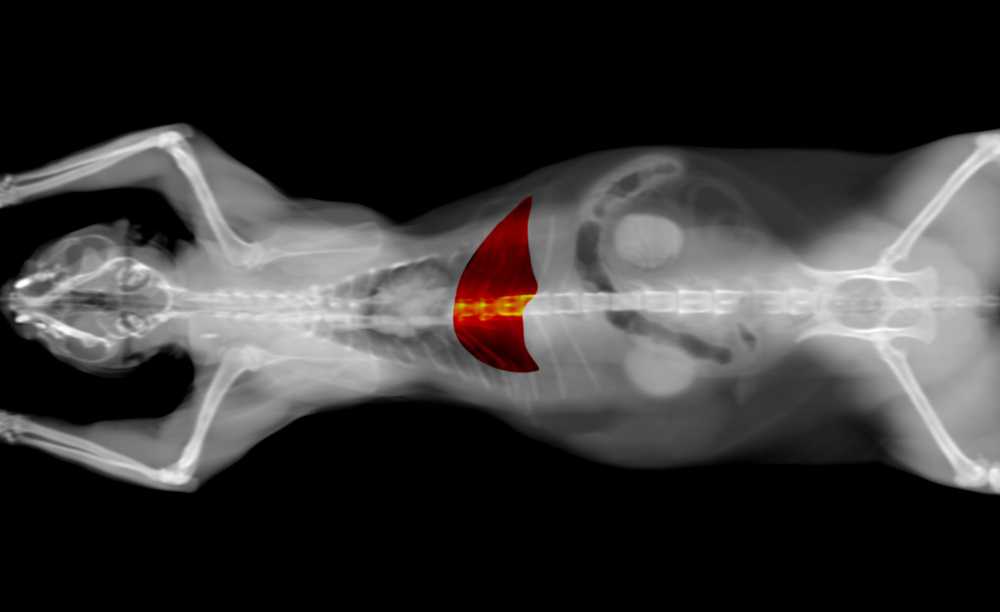

Для диагностики опухолей печени используются рентгенографические исследования, УЗИ, магнитно-резонансная томография (МРТ), компьютерная томография (КТ) и сцинтиграфия.

Результаты, полученные указанными методами диагностики играют ведущую роль при постановке окончательного диагноза. При этом ведущими задачами диагностики являются определение локализации опухоли, ее вид, степень инвазии опухоли в окружающие ткани и состояние лимфоузлов ворот печени.

При использовании современной аппаратуры рентгенографическое исследование органов брюшной полости в латеральной и вентро-дорсальной проекциях позволяет визуализировать опухоли в 86% и 73% случаев, соответственно.

УЗИ позволяет дифференцировать солидные образования и кисты, гемангиомы и злокачественные опухоли. Метод высоко информативен для определения локализации поражения и распространенности процесса.

Эхографическое изображение новообразований печени зависит от их типа и стадии развития. Печеночноклеточный рак визуализируется в виде единичных или множественных образований неправильной формы с неоднородной эхоструктурой, окруженных тонким гипоэхогенным ободком (рис. ). Капиллярная гемангиома на эхограмме представляется в виде овальных образований с повышенной эхогенностью и ровными четкими краями. Часто визуализируются также питающие опухоль кровеносные сосуды (рис. ). Кавернозная гемангиома характеризуется неоднородной внутренней структурой и наличием эхонегативных зон различной формы и разного размера (рис. ). Метастазы визуализируются в виде единичных или множественных образований неопределенной формы с неопределенной структурой и неровными краями. При наличии некроза и распада опухоли на эхограмме выделяется участки паренхимы печени со смешанной эхогенностью.

Компьютерная томография в настоящее время в гуманной и ветеринарной практике считается одним из классических методов диагностики различных новообразований печени(4, 6,7).

Магнитно-резонансную томографию можно считать одним из лучших методов выявления новообразований печени. Однако, из-за отсутствия аппаратов МРТ в ветеринарной практике он используется крайне редко.

К современным методам оценки функционального состояния печени в гуманной медицине является динамическая сцинтиграфия, которая заключается в введении больному изотопа препарата радия и одновременном проведении динамической сцинтиграфии. Этот метод позволяет точнее определить поглотительно-выделительную функцию печени, оценивая ее функциональные возможности. К сожалению, в доступной литературе данных об использовании данного метода в ветеринарной практики мы не обнаружили.